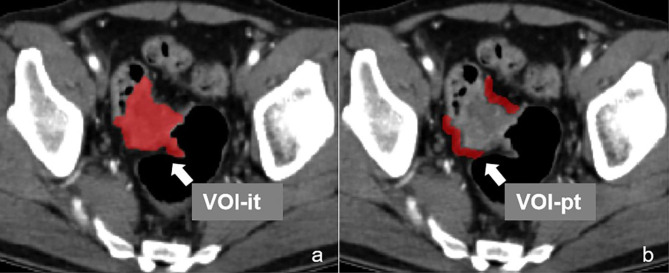

CT-based machine learning radiomics analysis

Before radiomics analysis, the volume of interest (VOI) of intratumor (VOI-it) and peritumor (VOI-pt) was depicted after three steps: (1) standardize the original CT images through the methods of reconstructing the voxel of X/Y/Z axes into 1.0 mm and adjust the image grayscale into 1 to 32 in software of A.K. (Artificial Intelligence Kit, GE Healthcare). (2) load the standardized triphasic CT images into ITK-SNAP software (https://www.itksnap.org/, Version3.4.0 ), the VOI-it (Fig. 2a) was segmented manually by two radiologists with 7 and 10 diagnostic experience. (3) the VOI-pt (Fig. 2b) was obtained by expanding 5 mm from the margin of tumor in A.K. software.

Fig. 2.

The VOI-it (a) and VOI-pt (b) was delineated in software of ITK-SNAP